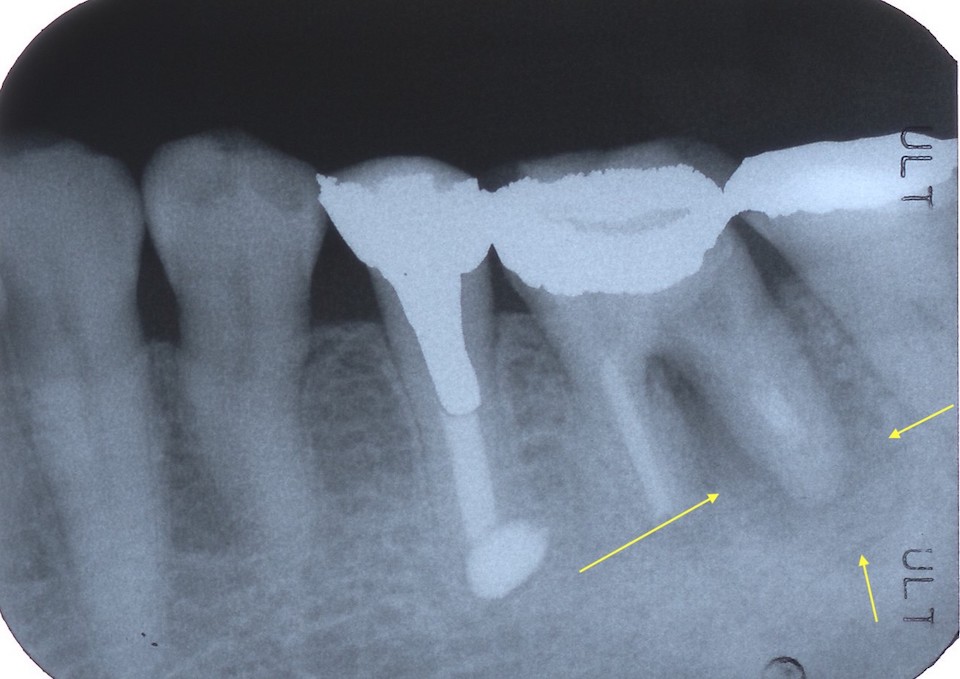

今日の抜歯再植術シリーズ34.0

60代女性、左下6、歯根破折、GA久しぶりの再植ネタというか臨床ネタだ。数年前も腫れて歯根にクラックが入っているのを確認していた。当時の画像があったらアップしてみたい。まずはレントゲン写真でのbefore/afterからbefore黄色矢印に囲まれた部分が肉芽というか膿瘍というか、大きな炎症性組織がある部分。after腫れている遠心根のみ分割抜歯の予定。冠が外れると歯根が割れているのが見える。歯根端に大きな膿瘍が付着していて、ズルズルと一緒に抜けてくる。膿瘍を掻爬して3MIX+生食水で洗浄しておく。両隣に維持溝を掘っておく。膿瘍はハサミで切除し、破片を合わせてみた。割れた歯根は3ピースだ。つづく